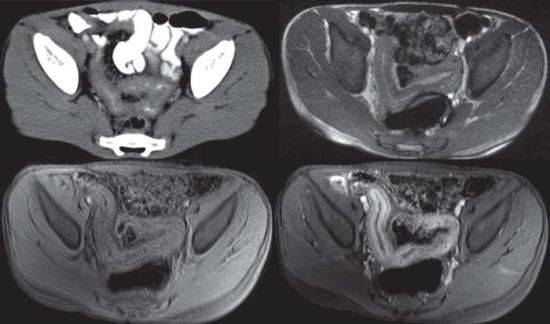

In a pictorial essay, Majid Chalian, MD, and colleagues at Johns Hopkins University said computed tomography (CT) has proven its value for the evaluation of IBD especially because this cross-sectional imaging technique allows identification of both intra- and extraluminal lesions and complications. But the high radiation dose limits its use in the pediatric population. They wrote that MRI “seems to be exquisitely well suited for the diagnostic workup of children with IBD” as a result.

New developments in MR enterography have been key, they said. Until recently, MRI was limited by long acquisition times and a lack of oral contrast agents that could adequately distend the bowel. With the development of fast T1- and T2-weighted MRI sequences and hyperosmolar biphasic (i.e., T1 hypointense, T2 hyperintense) oral contrast agents like barium preparation or polyethylene glycol, high-resolution images of the bowel can now be acquired. The simultaneous IV injection of glucagon further enhances image quality because bowel motion is suppressed.

The researchers further said MR enterography provides superior soft-tissue contrast, renders multiple imaging contrasts, can be acquired in multiple planes, gives an excellent depiction of fluid and edema, allows accurate differentiation of inflammatory strictures from fibrostenotic strictures, and has a high sensitivity for detecting mucosal changes.